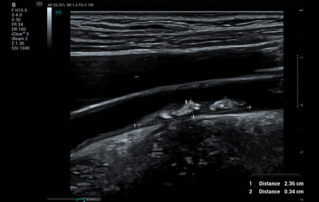

Female pelvic floor anatomy, which developed since the early 20th century, has had a variety of theories, including integral theory, three levels of vaginal support theory, "hammock hypothesis", and three-chamber system. Supporting structures such as pelvic floor muscles, fascia and ligament play an important role in maintaining the normal function of pelvic floor, among which levator ani muscle group is one of the most important supporting structures.